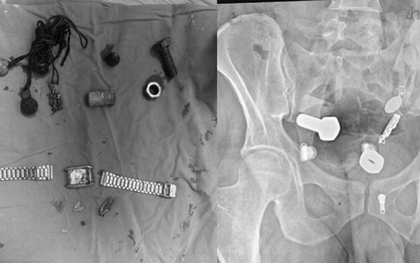

Bệnh nhân 15 tuổi nhập viện vì sốt và đau bụng dữ dội, các bác sĩ đã phẫu thuật cấp cứu thành công, cảnh báo về nguy cơ biến chứng nguy hiểm của ký sinh trùng.